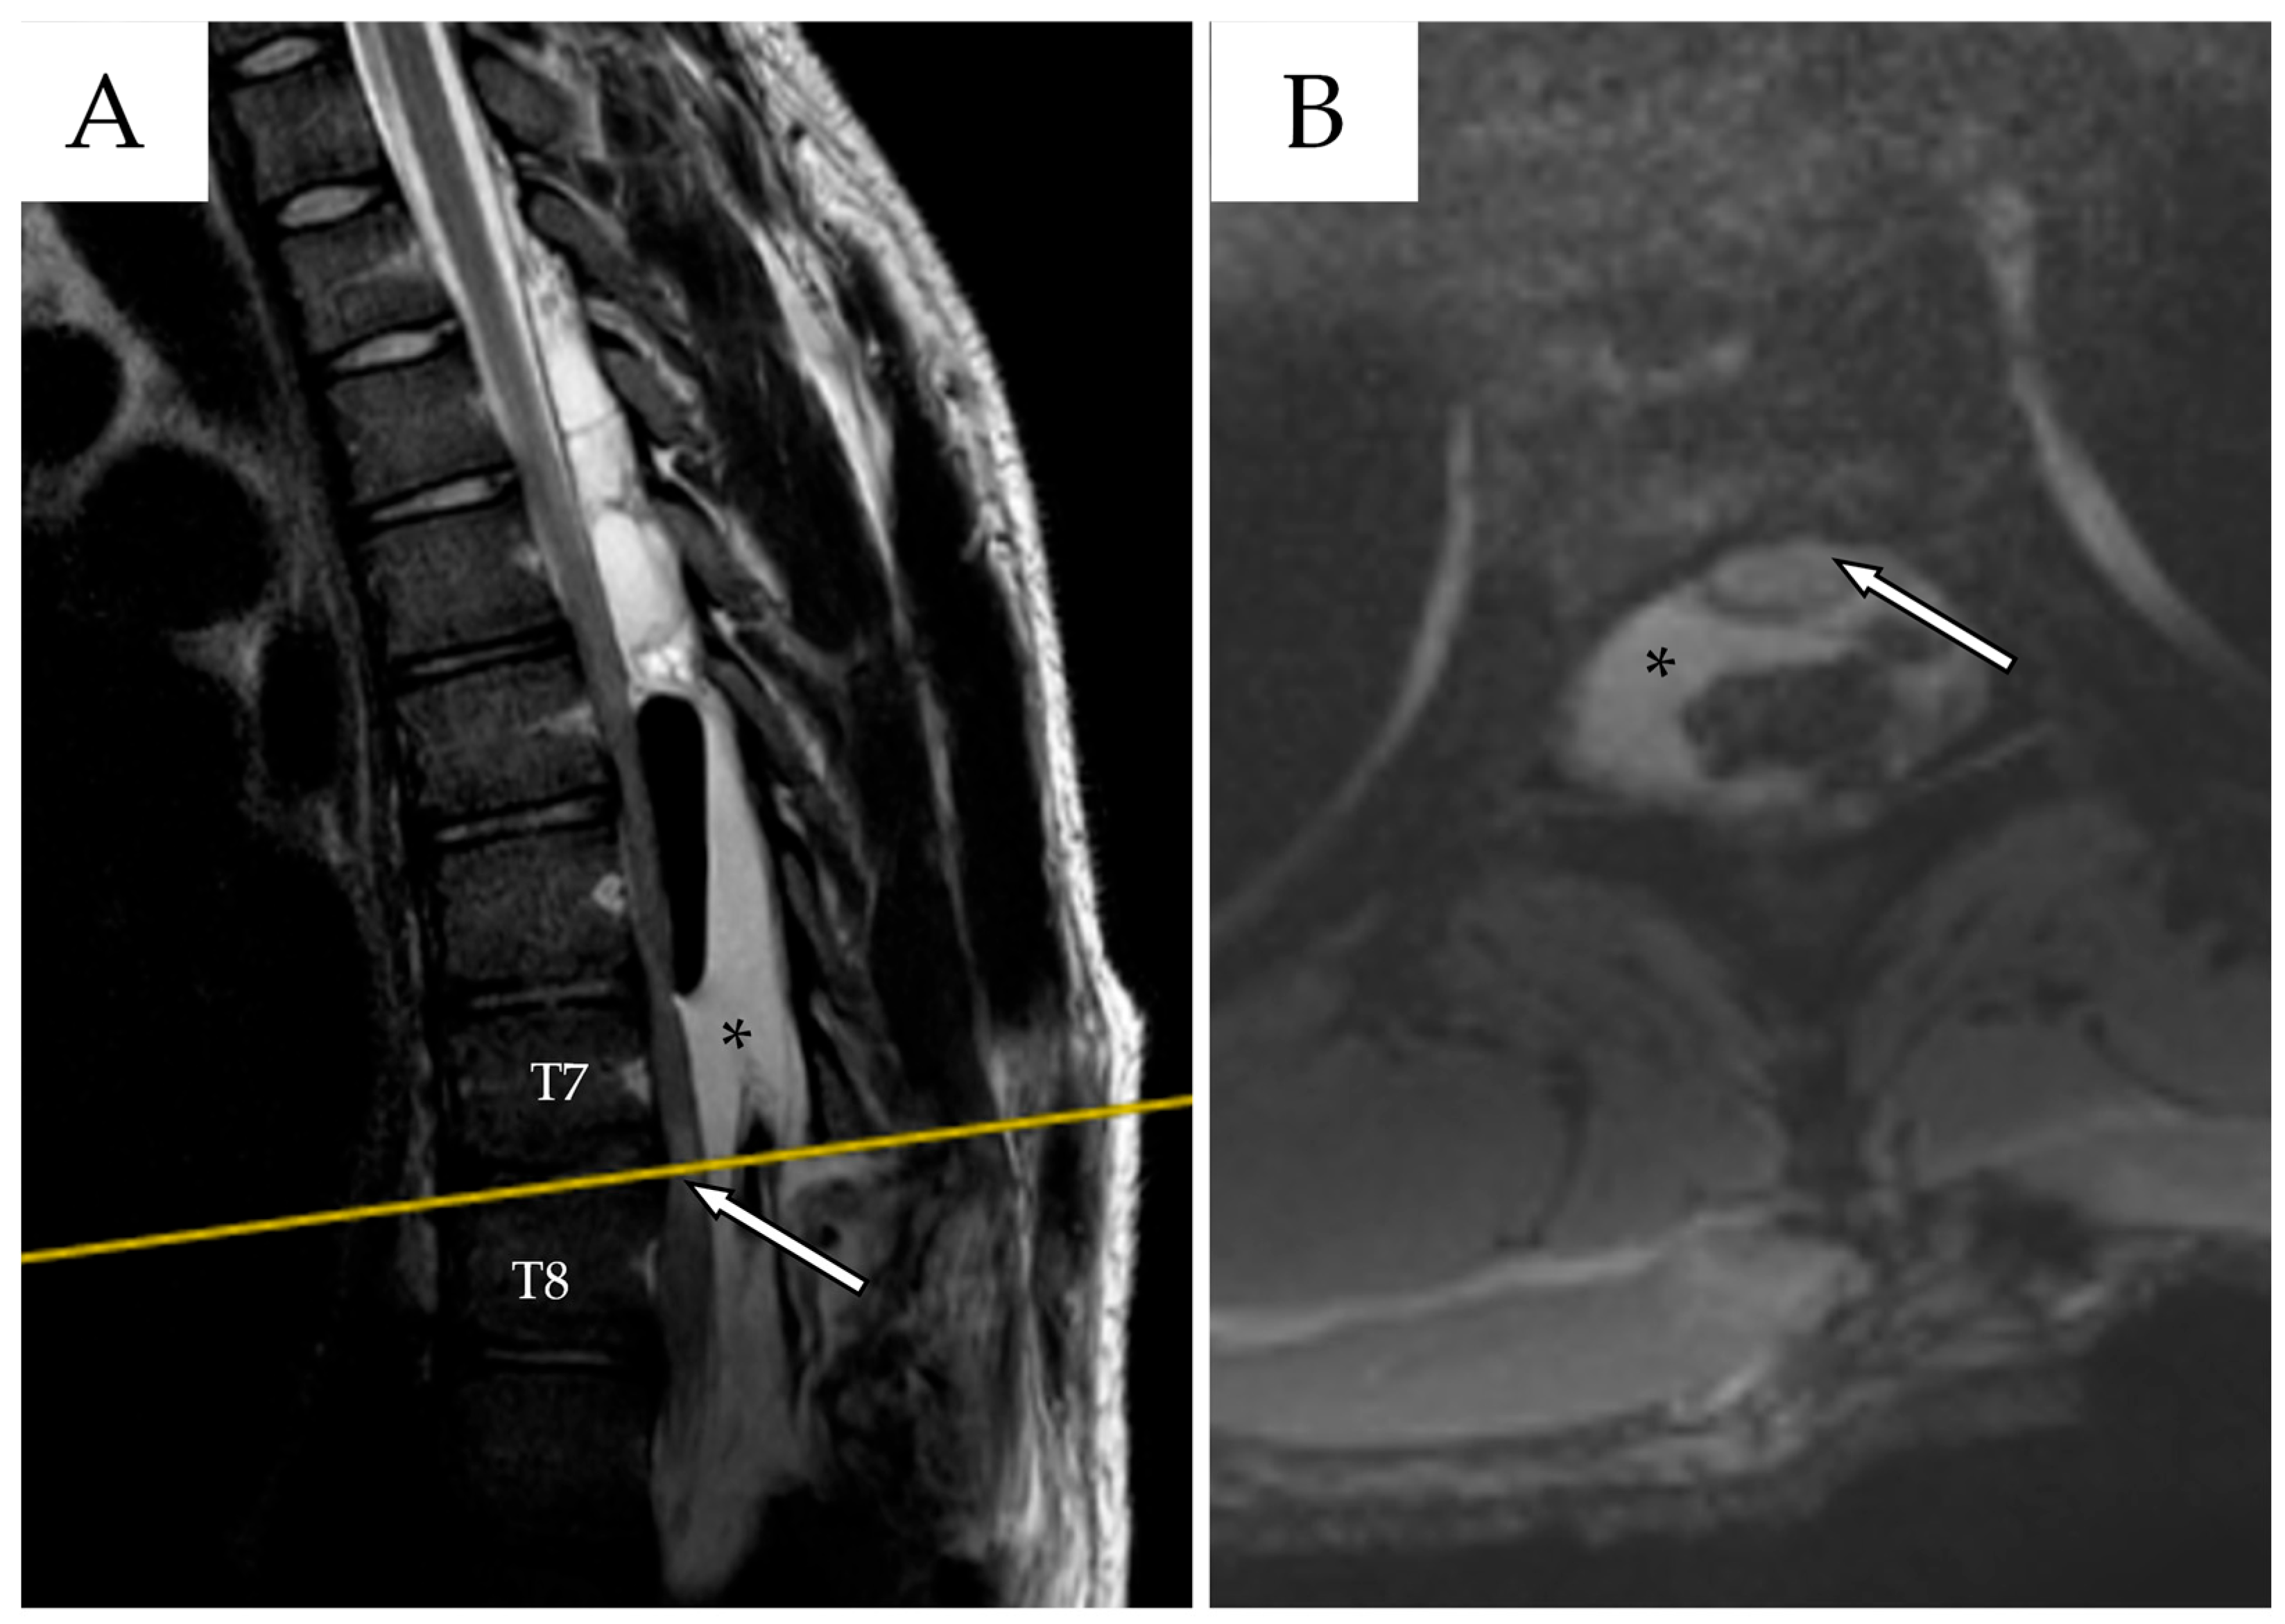

2.3. Second Admission

2.4. Second Follow-Up